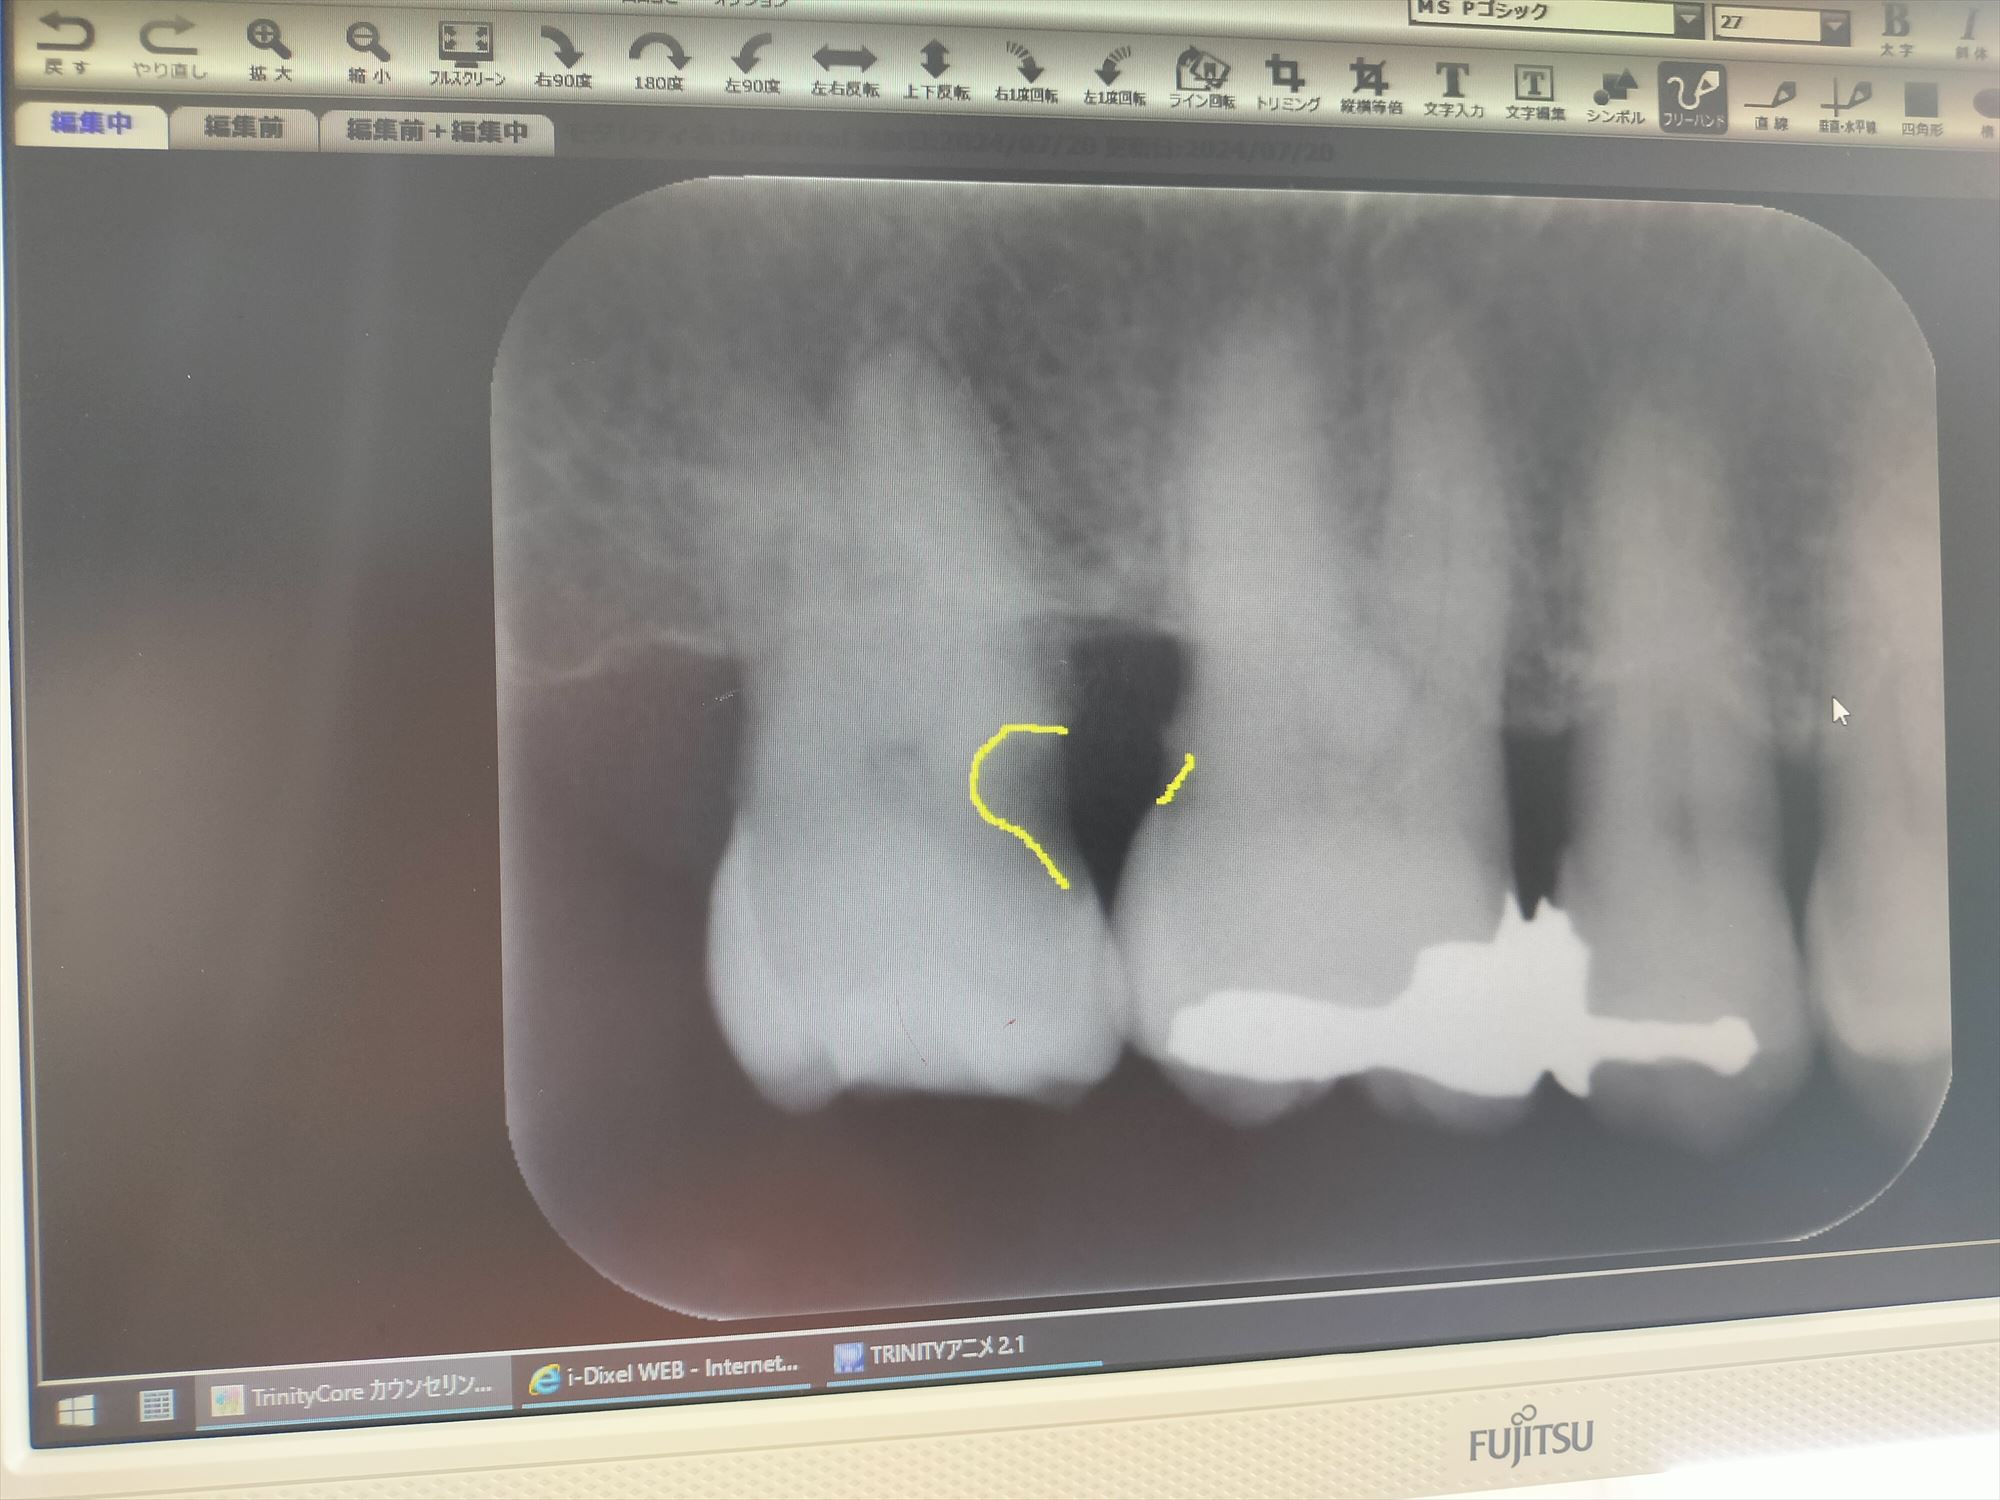

2024年7月5日(金) 右上奥歯の虫歯が痛んだ

2024年6月7日(金) 銀冠